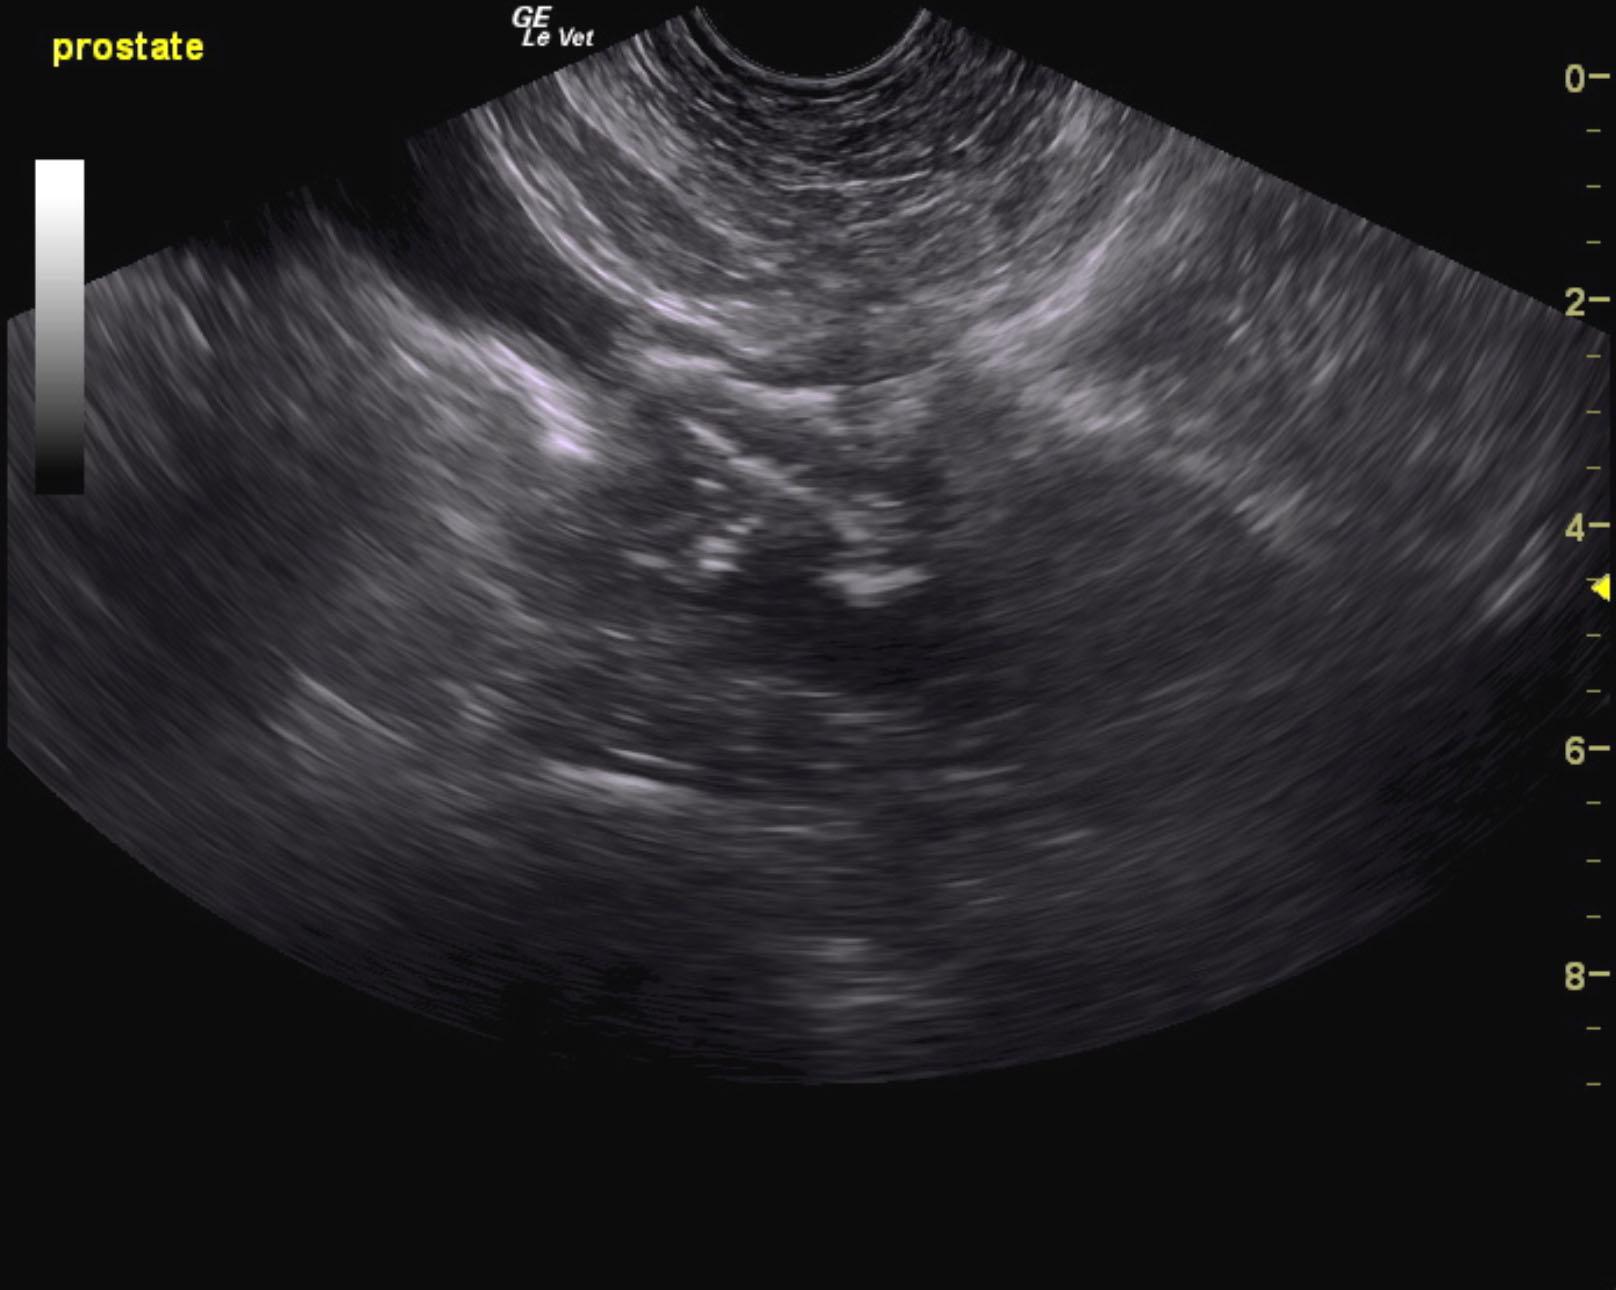

Mineralizing prostatic mass extending into the cystourethral junction.

The prostate in this patient revealed a mixed, hypoechoic and multifocally mineralizing mass that measured 2.5 cm. Ultrasound-guided FNA or traumatic catheterization is recommended for confirmation. Pericapsular inflammatory pattern was noted around the prostate with proliferative tissue noted cranial to the point of the cystourethral junction.

sebastian_dimurro_beagle_6_yr_prostatic_carcinoma_2vlcsnap-2015-12-25-12h06m00s138